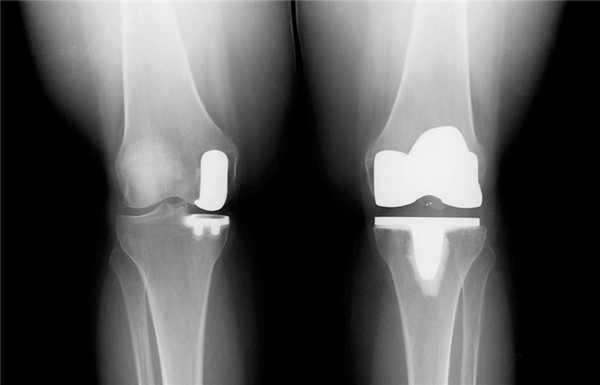

Замена коленного сустава: что это, видео-фото операций, технологии, сроки восстановления

Замена коленного сустава (ЗКС) - метод хирургического лечения последствий дегенеративно-дистрофического патогенеза колена. Цель операции полное восстановление функций проблемного отдела конечности за счет замены необратимо пораженного сочленения эндопротезом. Гонартроз 3-й степени (в 85% случаев) самая частая причина.

Артроз коленного сустава на рентгене.

Посмотрите на рентген, на нем вы видите, до какой степени при запущенном гонартрозе изношен гиалиновый хрящ, обеспечивающий гладкое скольжение суставных поверхностей. Концевые участки костей грубо деформируются нарушая функции сгибания и разгибания конечности вызывая интенсивный болевой синдром.

Сравнение здорового и пораженного сустава.

Две техники операции у одного пациента.

Одномыщелковая замена сустава на рентгене.

Сравнение двух типов операций.

Рентген после операции. Протез стоит корректно.